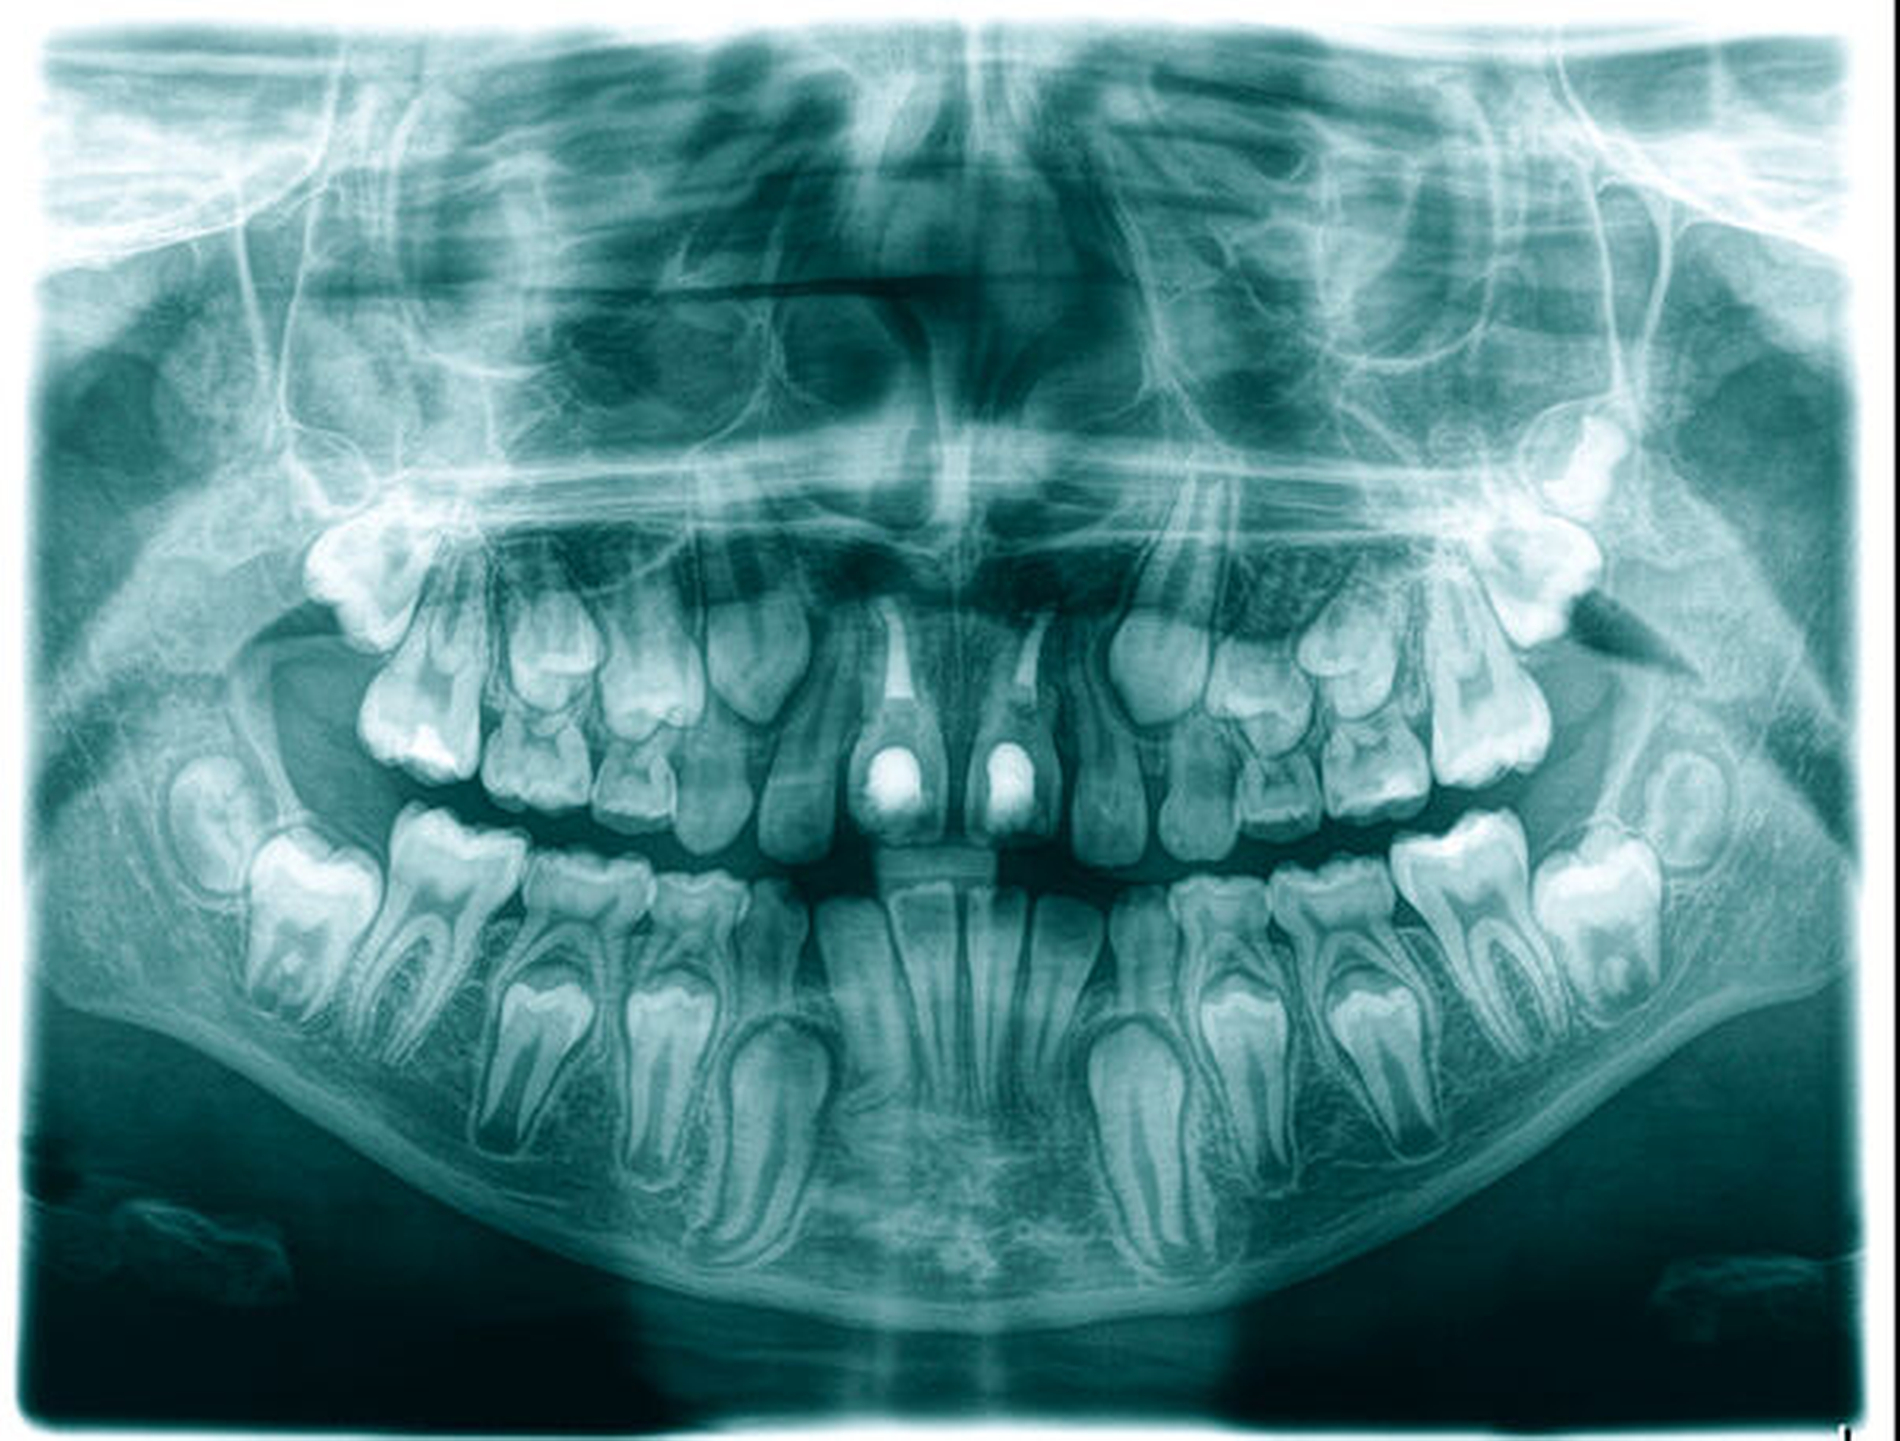

Die Häufigkeit für den Frontzahnverlust beträgt drei bis vier Prozent. Die Altersgipfel liegen zwischen dem achten und dem neunten sowie vom zwölften bis zum 14. Lebensjahr. Betroffene Zähne sind der mittlere und der seitliche Schneidezahn im Oberkiefer. Es besteht eine Korrelation der Häufigkeit zu den Zahnstellungsanomalien der vergrößerten sagittalen Schneidekantenstufe, dem schmalen Deckbiss mit protrudierten seitlichen Schneidezähnen und progen stehenden Einzelzähnen. Obwohl bei Avulsion die sofortige Reimplantation zum Erhalt des Zahnes führen kann, sind häufig Ankylosen des Parodonts und Wurzelresorptionen mit begrenzter Erhaltungswürdigkeit die Folgen. Eine fehlende Sensibilität, ein hoher Klopfschall und der röntgenologische Resorptionsnachweis sind diagnostische Anzeichen dafür.

Zeitpunkt und Auswahl des Transplantats

In der Regel sollte bei einem Frontzahnverlust im Oberkiefer ein Prämolar mit einer Wurzel verwendet werden. Die Wurzel einwurzeliger Prämolaren und deren Form sind in einer Schneidezahnalveole passfähiger und geeigneter für die parodontale Regeneration als ein Prämolar mit zwei Wurzeln. Der Prämolar sollte nach Möglichkeit aus dem Unterkiefer entnommen werden, da bei einem Misserfolg zwei Zähne innerhalb eines Kiefers fehlen würden. In der Regel wird die Extraktionslücke kieferorthopädisch mittels skelettaler Verankerung geschlossen. Zuvor ist die Anlage des dritten Molaren im betreffenden Quadranten zu prüfen, der nach kieferorthopädischer Einstellung mit dem zweiten Molaren des Oberkiefers okkludiert.

Das Wurzelwachstum des Transplantats sollte zum Zeitpunkt der Entnahme nicht mehr als zwei Drittel betragen. Dies kann eine operative Freilegung notwendig machen (Abb. 3).